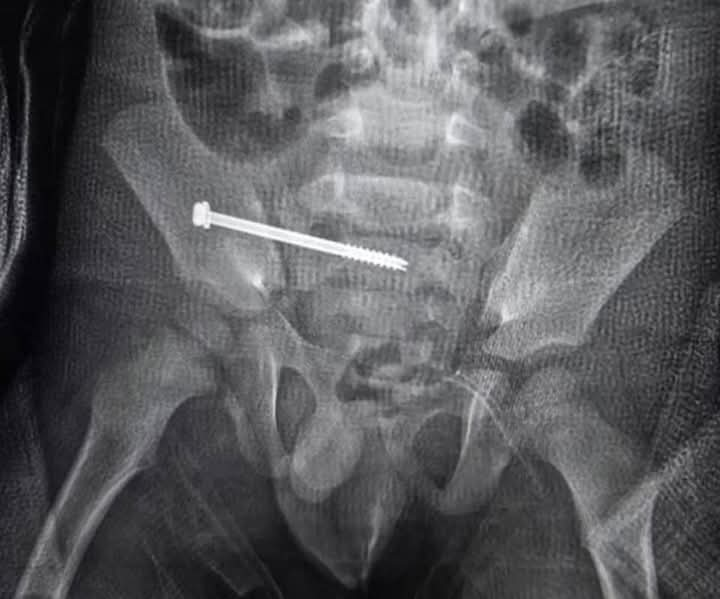

أكَّد الدكتور سمير الشورى، رئيس قسم جراحة العظام بكلية طب بنين جامعة الأزهر بدمياط، أن فريقًا طبيًّا من القسم نجح — بفضل الله — في إجراء عملية نادرة على مستوى العالم، تمثَّلت في تثبيت كسر مع خلع عمودي ما بين الحوض والعمود الفقري لطفل يبلغ من العمر ثلاث سنوات، نتيجة حادث دراجة بخارية.

وأوضح الدكتور الشورى أن العملية أُجْريت دون فتح جراحي، باستخدام مسمار تثبيت بين الحوض والعمود الفقري، وهي تقنية دقيقة للغاية تتطلب مهارة عالية وخبرة متقدمة، وقد أُجريت العملية بنجاح على أيدي فريق طبيٍّ متميز بقيادة الدكتور عثمان الشَّريف، أستاذ جراحة العظام بالقسم، وبمشاركة نخبة من أعضاء هيئة التدريس والهيئة المعاونة بالقسم.